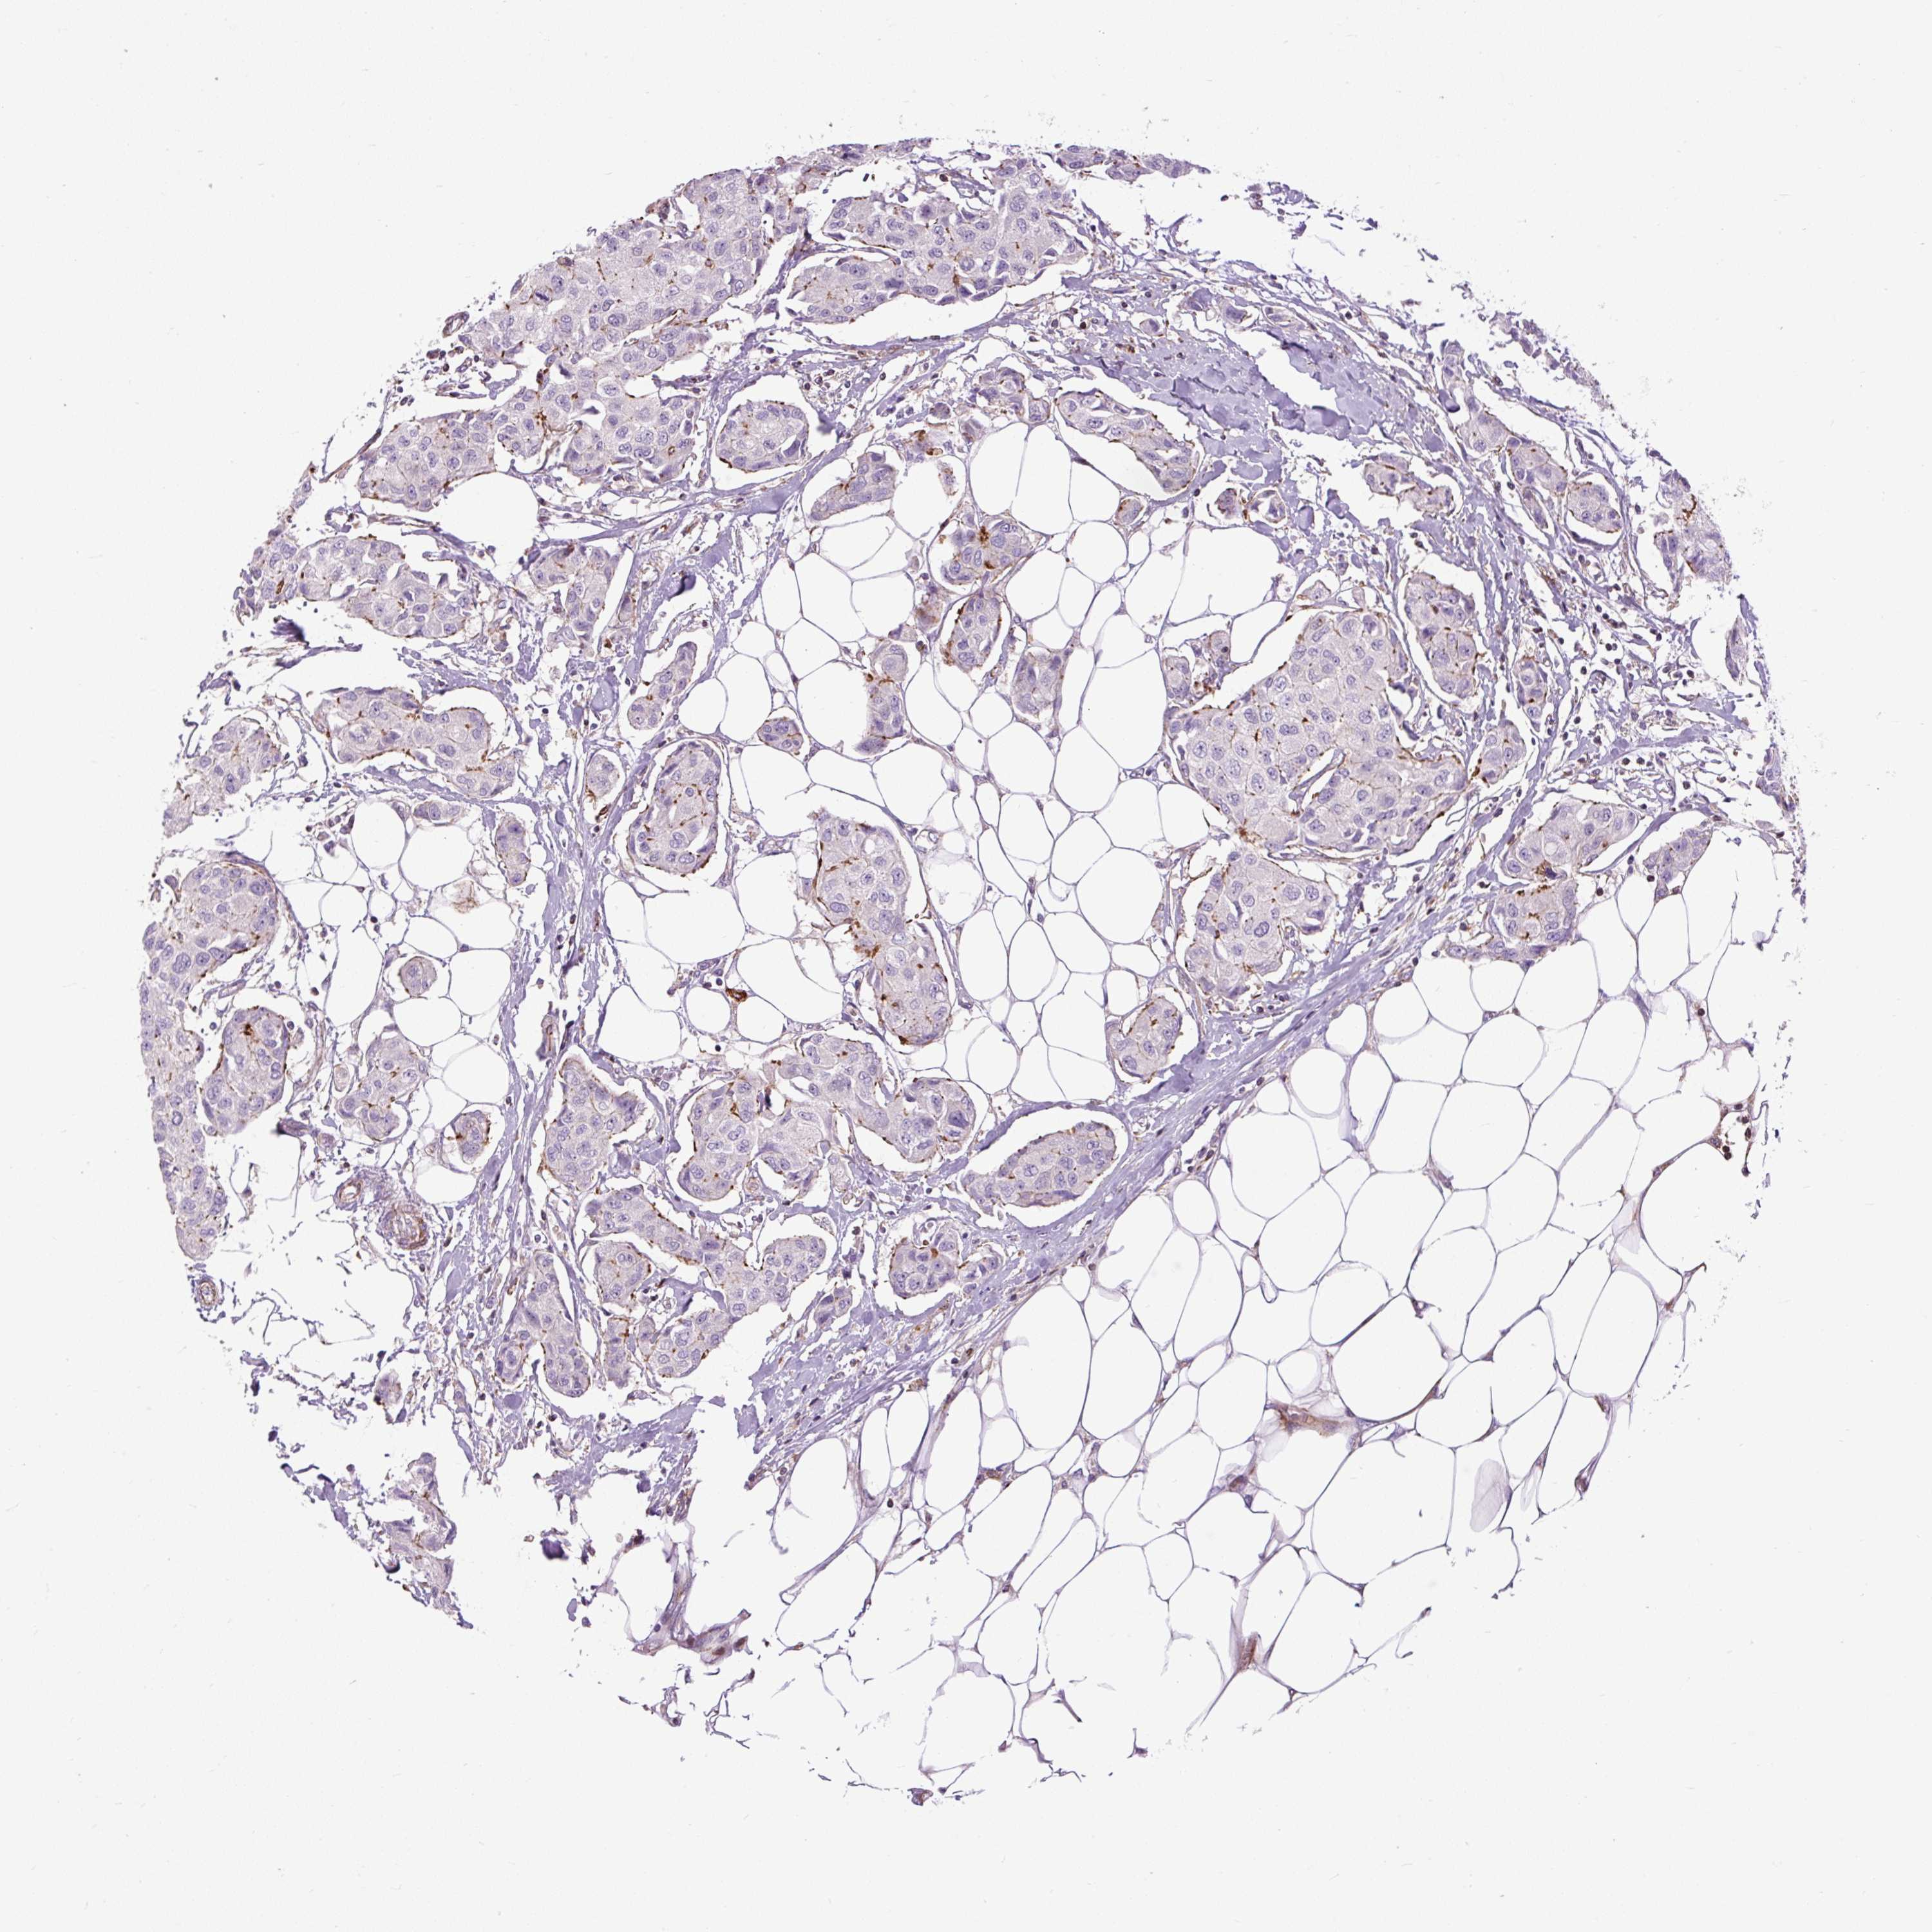

CANCER BREAST CANCER Show tissue menu

Breast cancer

Human cancer